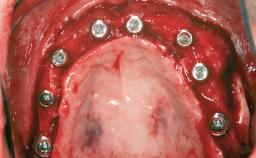

Le Fort I Interpositional Graft and Mandibular Sandwich Osteotomy for Maxillofacial Rehabilitation after Severe Periodontitis

A 47-year-old woman who had suffered from aggressive periodontitis requiring a number of periodontal interventions over more than 10 years was referred by her general dental practitioner and periodontologist for bone augmentation and implant therapy. Her failing dentition had already been scheduled for extraction. The patient expressed a desire for implant-supported fixed restorations and esthetic improvement of her lower face. She had agreed to consult with a maxillofacial surgeon after the referring dentist had suggested bone augmentation. An initial examination by the maxillofacial surgeon revealed mobility of all residual teeth in a patient who was very unhappy with the function of her removable partial dentures. Due to periodontally migrated flaring teeth and loss of occlusal support, the vertical dimension of occlusion was dramatically reduced. The patient was displeased with her lower face because of deepened nasolabial, commissural, and supramental folds.

# of Implants 14